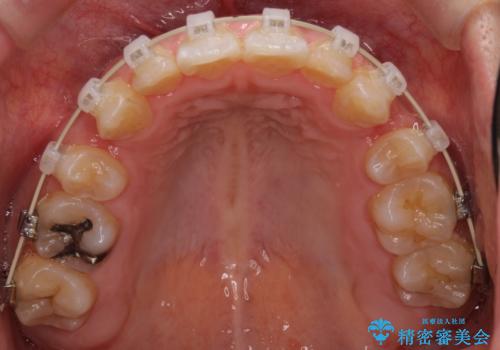

- 矯正装置

- クリアブラケット

上顎両側と左下の前から4番目の歯と、右下の乳歯を抜歯して矯正することとなりました。

乳歯を抜歯することにより、通常よりは治療期間を要してしまいましが、前歯のガタガタもなくなりきれいな歯並びになったと喜んでいただけました。